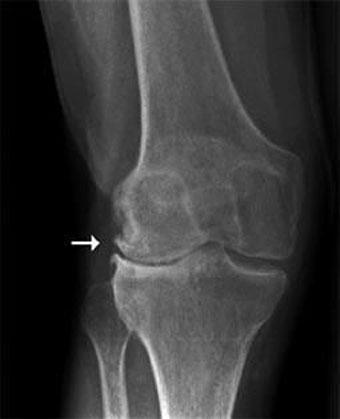

Os osteófitos são visíveis na radiografia em forma de uma protuberância óssea (um “chifrinho”). Habitualmente, os osteófitos em si não necessitam nenhum tratamento.

O que é importante é diagnosticar e tratar a artrose e suas consequências musculares, tendíneas e ligamentares em torno da articulação, para que a pessoa volte a ter um estilo de vida saudável. Abaixo, algumas imagens de livros e em raios-x, pra que agora todos possam identificar um osteófito quando for mencionado pelo profissional da área de saúde que lhe está atendendo.

Osteófitos vistos pelos raios-x em um joelho direito em processo de artrose.

Os osteófitos podem aparecer na patela também, como demarcados acima.